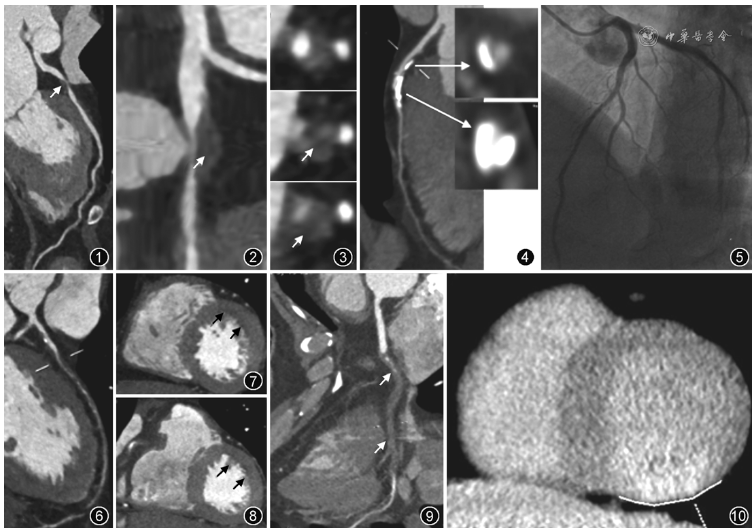

(2)高危斑块:病理研究表明,急性冠状动脉综合征,包括心源性猝死、急性心肌梗死和不稳定心绞痛,是继发于斑块破裂和侵蚀导致的急性冠状动脉血栓形成,或者慢性病变导致的管腔严重狭窄。这些斑块特征在CCTA上有以下表现。①低衰减斑块:密度<30 HU的斑块(low-attenuation plaques,LAP)(图1)。②管腔阳性重构(positive remodeling,PR),即病变处最大血管直径与近端正常血管段的管径比值>1.1(图2)。具有这两种CT特征的斑块称为两特征阳性斑块(2-feature-positive plaques,2-FPP)。③环状坏死核心(餐巾环征):低CT衰减的中心区域,明显与管腔接触并被一圈高衰减包围(图3),与光学相干断层成像(optical coherence tomography,OCT)验证的薄纤维帽和未来主要不良心血管病事件(major adverse cardiac events,MACE)密切相关。④点状钙化:在任何方向上直径<3mm的小灶性钙化。需要特别指出的是发现易损斑块需要进行危急值上报,告知患者及时就医,也提示临床医师做好风险评估,及时进行干预治疗。

另外,钙化一直是CCTA诊断中遇到的难以解决的最大问题,由于线束硬化伪影及部分容积效应,钙化斑块体积被夸大,更加影响管腔观察和狭窄程度判断。对于钙化病变的管腔判断,要结合长轴和短轴图像仔细分析,避免出现凡是钙化管腔都无法评估和/或凡是钙化管腔都存在狭窄这两个极端判断。通常情况下,无论长轴或者短轴,钙化斑块处的管腔若能够显示,则狭窄程度通常不重(图4),由冠状动脉造影证实(图5);若钙化弥漫成环形或满月形完全遮挡管腔,则报告提示管腔评价受限;若钙化斑块同时合并非钙化成分存在,则管腔存在有意义狭窄的可能性较大。

对比剂首次通过左心室心肌时,灌注减少的心肌节段形成特征性低衰减区。冠状动脉重度狭窄或闭塞时(图6),应注意观察其下游供血区心肌是否存在心内膜下灌注减低(图7,8)。当CCTA图像上提示患者具有重度狭窄(>70%及以上狭窄)或者两支或者3支病变时(图9),建议进行CCTA延迟强化扫描,显示与病变血管相对应的供血心肌处的延迟强化,提示心肌纤维化(图10)。

图1~3 冠状动脉高危斑块CT表现。患者,女,52岁,活动后胸痛,休息后缓解1个月余。冠状动脉CT曲面重组显示前降支近段非钙化斑块(图1↑);该斑块内见低密度区(图2↑),测量CT值最低为20HU,管腔呈正性重构,管腔重度狭窄;短轴显示该斑块为低衰减斑块,内见低密度区(图3↑)

图4,5 冠状动脉钙化斑块狭窄程度评估图像。患者,男,61岁,间断胸闷。图4为CT图像,曲面重组显示前降支近段钙化斑块,放大后横轴位(↑)显示两处钙化斑块均可见周边管腔,提示管腔无有意义狭窄;冠状动脉造影证实管腔无明显狭窄(图5)

图6~8 冠状动脉重度狭窄者心肌改变的CT表现。患者,男,58岁,发作性胸痛10年,加重1个月余。冠状动脉CT曲面重组显示前降支弥漫非钙化为主斑块,管腔重度狭窄(图6);左心室短轴CT图像(图7,8)显示前壁心内膜下心肌密度减低,提示心肌缺血(↑)

图9,10 冠状动脉闭塞患者心肌延迟CT表现。男,49岁,冠状动脉CT曲面重组显示右冠状动脉中远段闭塞(图9↑);CT延迟扫描左心室短轴位显示左心室下壁延迟强化,提示心肌纤维化,与冠状动脉病变对应(图10白线)